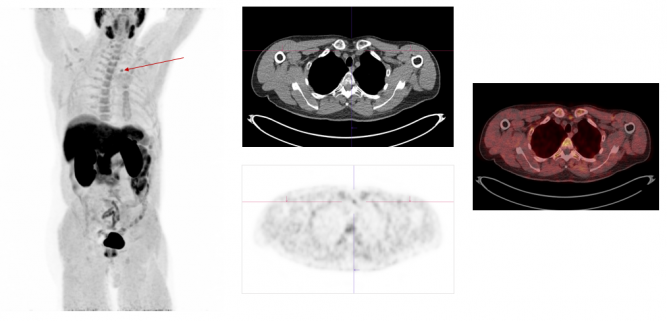

F-18-Cholin

F-18 choline is a nuclear medicine procedure that can be used to image parathyroid adenomas. .

- F18-Cholin